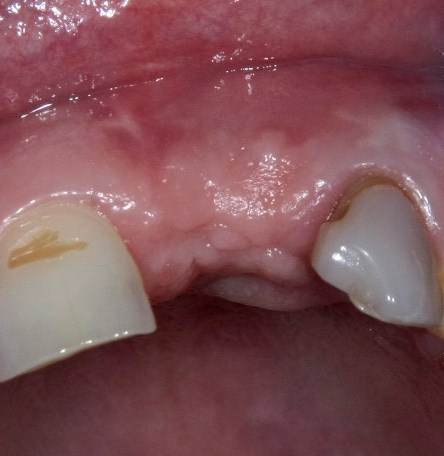

Другой вариант. Имплантируем, но существующего объема костной ткани недостаточно для получения адекватного эстетического и функционального результата:

Поэтому мы используем мембрану Geistlich BioGide и всё ту же аутокостную стружку:

Вот чем мне нравится мембрана BioGide — так это своими свойствами. Предсказуема до мелочей.

Во влажном состоянии она эластична и податлива, поэтому нет необходимости использовать пины или винты:

ну и, швы: